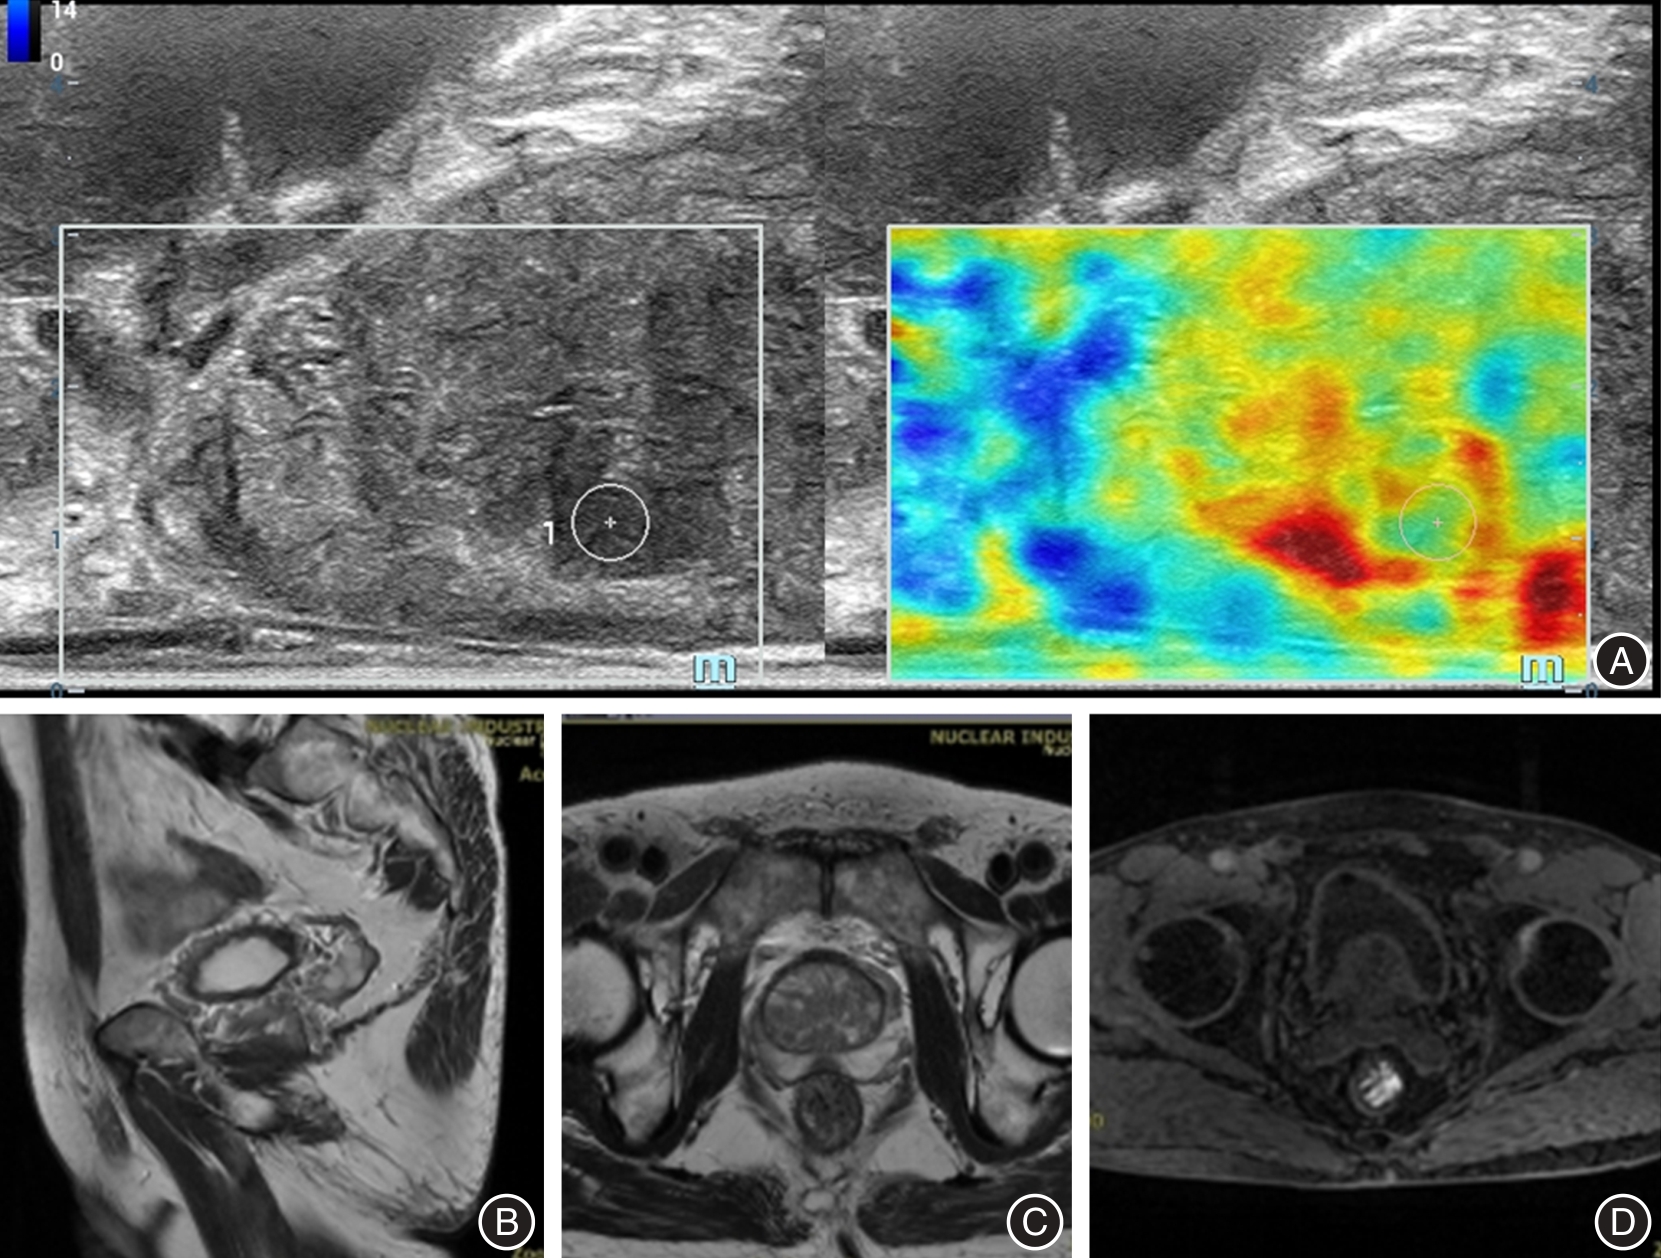

Objective To explore the application and imaging characteristics of transrectal real-time tissue elastography (TRTE) combined with magnetic resonance imaging (MRI) in the diagnosis of benign and malignant prostate lesions. Methods A total of 154 patients with suspected prostate cancer were collected and received TRTE and MRI. The imaging characteristics were analyzed, and the diagnostic value of TRTE and MRI on benign and malignant prostate lesions was evaluated with the pathological result of needle biopsy as the gold standard. Results Among the 154 patients, 79 malignant cases (prostate cancer, 51.30%) and 75 benign cases (benign prostatic hyperplasia, 48.70%) were pathologically diagnosed by needle biopsy. The malignant prostate lesions in the TRTE image were mainly manifested as lesions with a predominantly blue core (high stiffness, low strain), often with green margins or transitions (moderate strain, moderate stiffness). In MRI images, the lesions primarily exhibited low signal intensity on T2WI, high signal intensity on DWI, and low signal intensity on ADC, and early and obvious enhancement on DCE. Compared with patients with benign lesions, those with malignant lesions exhibited significantly older age and higher mean biopsy frequency, total prostate specific antigen (tPSA), prostate-specific antigen density (PSAD), SR scores and PI-RADS score (P < 0.05). Compared with clinicopathological diagnosis (gold standard), the diagnostic efficiency of TRTE and MRI based on binary classification showed no statistically significant difference in distinguishing benign from malignant prostate lesions (P > 0.05). Multivariate logistic regression analysis revealed that after adjusting for age and PSAD, TRTE elasticity score and MRI PI-RADS score were predictive factors for prostate malignancy (P < 0.05). Consequently, a prostate malignancy risk model was constructed as logit(P) = -0.421 + 0.072 × age + 0.087 × PSAD + 0.181 × elasticity score + 0.358 × PI-RADS V2.1 score. Taking the pathological diagnosis result as the gold standard, the sensitivities of TRTE, MRI and logistic regression model constructed by TRTE combined with MRI in the diagnosis of benign and malignant prostate lesions were 81.01%, 84.81% and 94.94%, and the specificities were 88.00%, 82.67% and 85.33%. The logistic regression model constructed by TRTE combined with MRI had the best diagnostic efficiency (area under the curve of 0,933). Conclusions The TRTE signs of lesions with a predominantly blue core and the MRI signs of T2WI low signal, DWI high signal, ADC low signal, DCE “fast in and fast out” enhancement are helpful to the diagnosis of benign and malignant prostate lesions. TRTE combined with MRI is helpful to enhance the diagnostic efficiency.